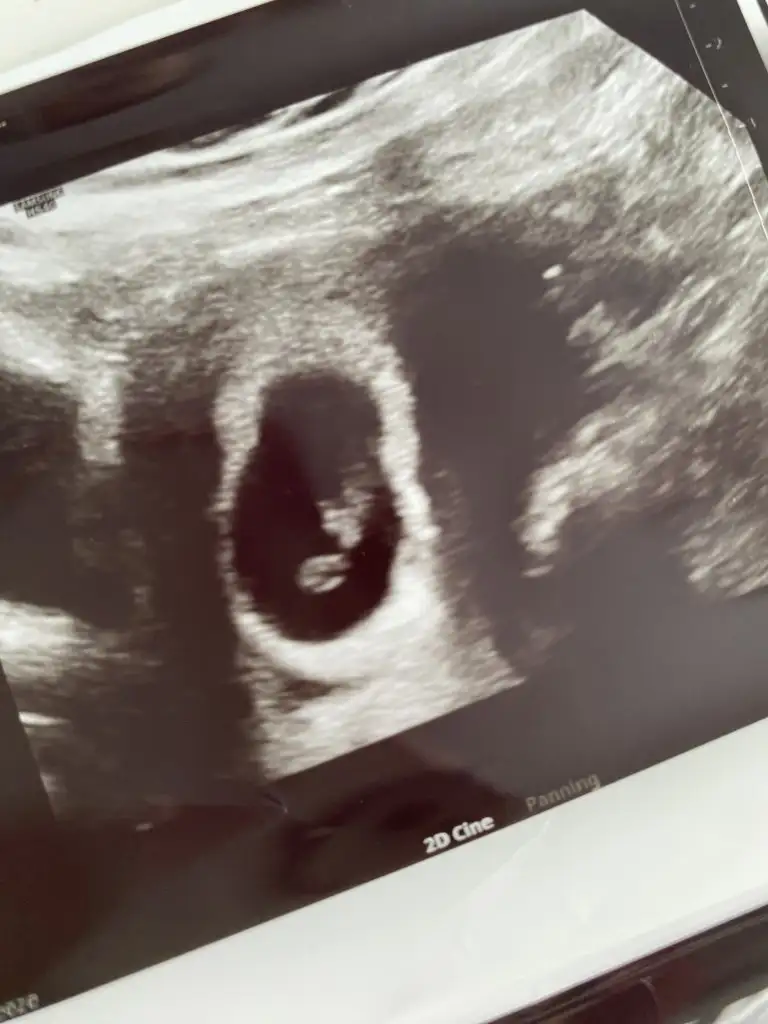

Karından ultrason bu arada

plesantası sağda bu yüzden kız aşkım :D

Bu bebişler neden hep ortada durur anlamadım azıcım plesentaya yakın dursalar olmuyor sanki 😂😂😂 kız gibi kuzum saglıkla gelsin inşallah başka var mı foto

Birde şöyle var tek olan diğer foto bide ikisini attım